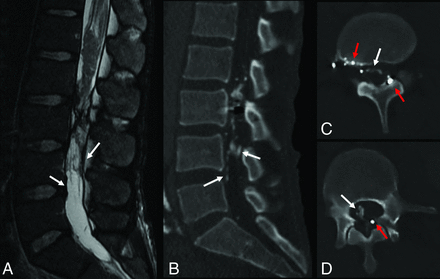

A 38-year-old male patient presenting 7 years following gunshot injury to the lumbar spine. Imaging from the time of the injury was unavailable for review. Sagittal T2-weighted MR imaging (A) demonstrates low signal thickening of the thecal sac as well as contour deformity of the thecal sac and its contents. Intermediate-signal tissue is present at the conus medullaris, relating to a posttraumatic scar. CT image (B) demonstrates peripheral and weblike ossification within the thecal sac (white arrows), which is not definitively identified on MR imaging (white arrows). The weblike ossification is better demonstrated on axial CT images (C and D), which also show multiple foci of metallic debris related to the prior gunshot injury (red arrows).